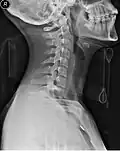

Vista lateral Radiografía del cuello con collarín cervical. -

Cuando las personas tienen una lesión traumática en la cabeza o el cuello, pueden tener una fractura cervical. Esto hace que corran un alto riesgo de sufrir lesiones en la médula espinal, que podrían agravarse con el movimiento de la persona y podrían provocar parálisis o la muerte. Un escenario común para esta lesión sería una persona sospechosa de tener un latigazo cervical por un accidente de tránsito.[2] Para evitar más lesiones, a estas personas se les puede colocar un collarín por parte de los profesionales médicos hasta que se puedan tomar radiografías para determinar si existe una fractura de la columna cervical.[3] El collarín cervical estabiliza solamente las siete vértebras superiores, de la C1 a la C7. (Se pueden utilizar otros dispositivos de inmovilización, como el dispositivo de extracción Kendrick o una tabla de respaldo para estabilizar el resto de la columna vertebral).